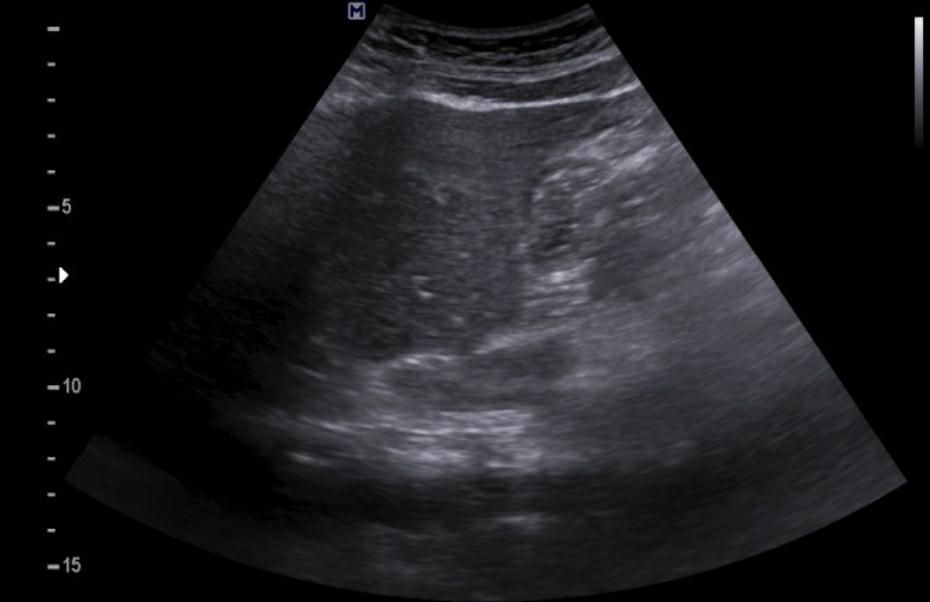

간에 혹이 있는건가요? 초음파 사진 봐주세요

간에 혹이 있는건지 맞다면 크기나 모양이 혈종인지 아이면 암으로 의심이 되는지 초음파 사진 봐주세요...ㅜㅜㅜ꼭 답변 부탁드립니다

• 3번 째 사진

간 초음파로만 봐서는 약간의 지방간이 관찰되지만 혈종으로 의심되지는

않으며 사진 우측에 보이는 동그란 부분은 장의 단면이 관찰되었을 가능성이

높은 것으로 보입니다